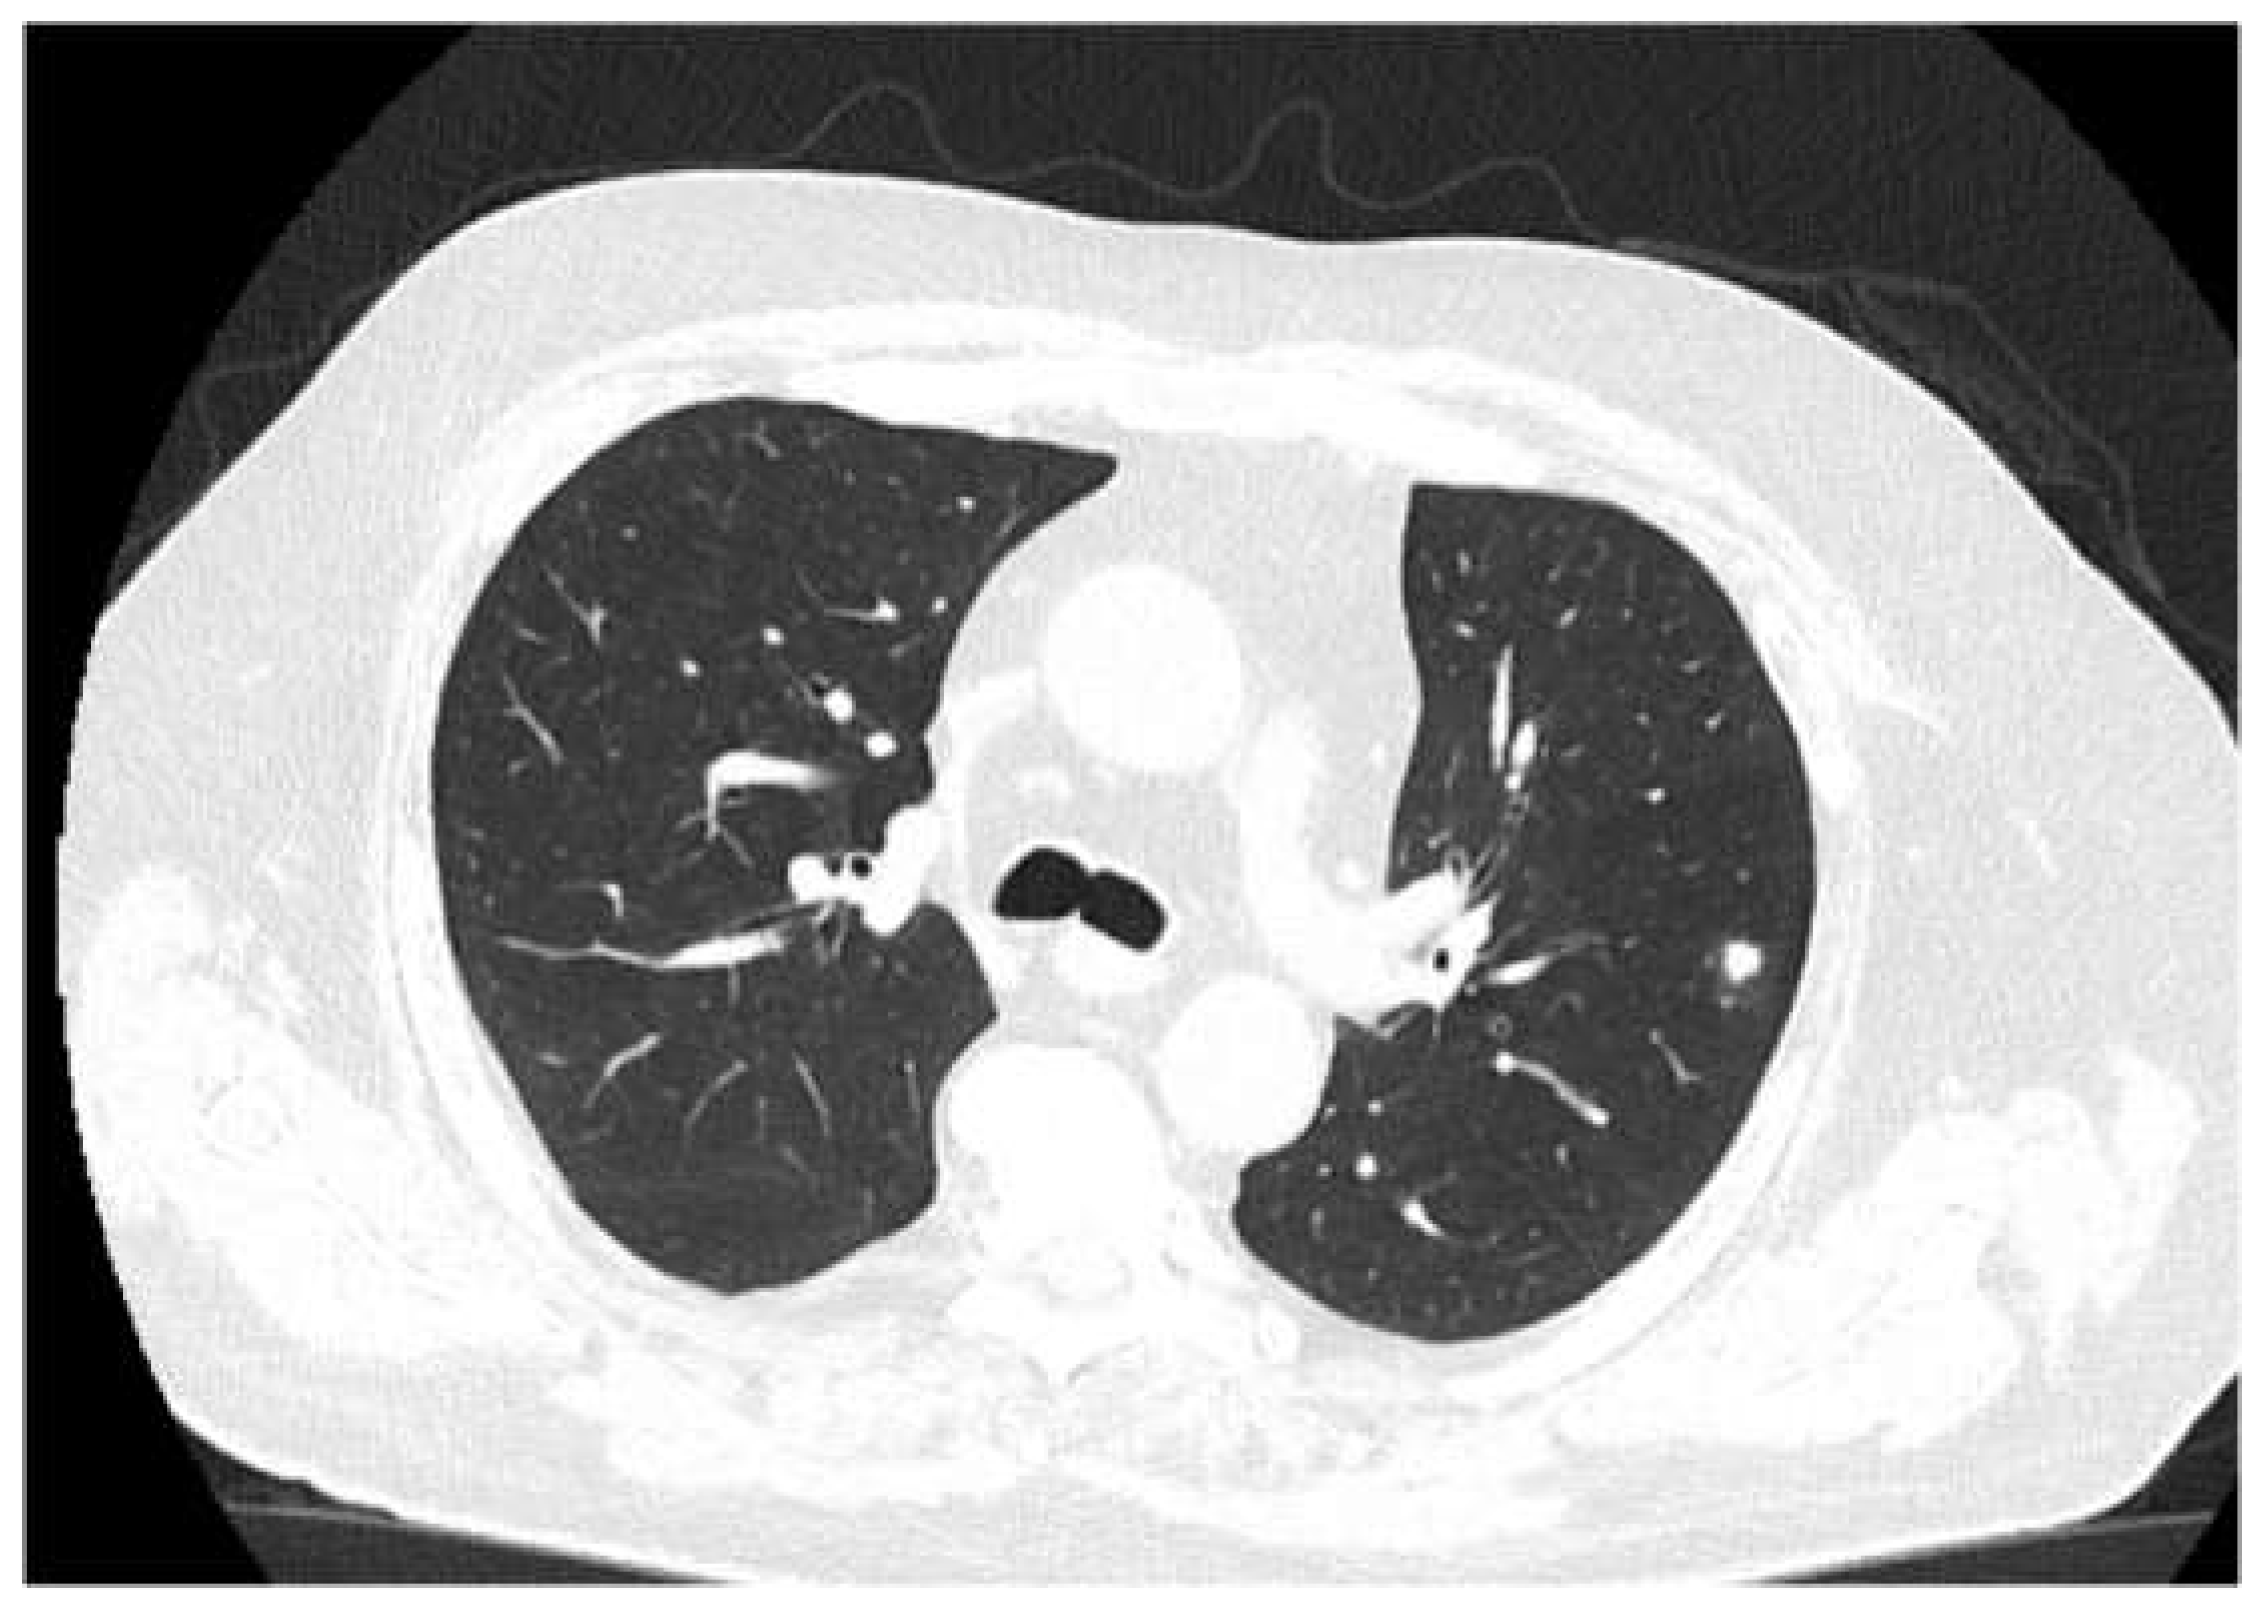

The patient received a follow-up brain MRI and chest CT (Figure 5) at 3 months, which showed complete remission of the brain abscess.

Figure 5. -Follow-up Ct at three months. The chest CT does not show any cavitating lesions, with residual scaring and healing processes of the lesions.